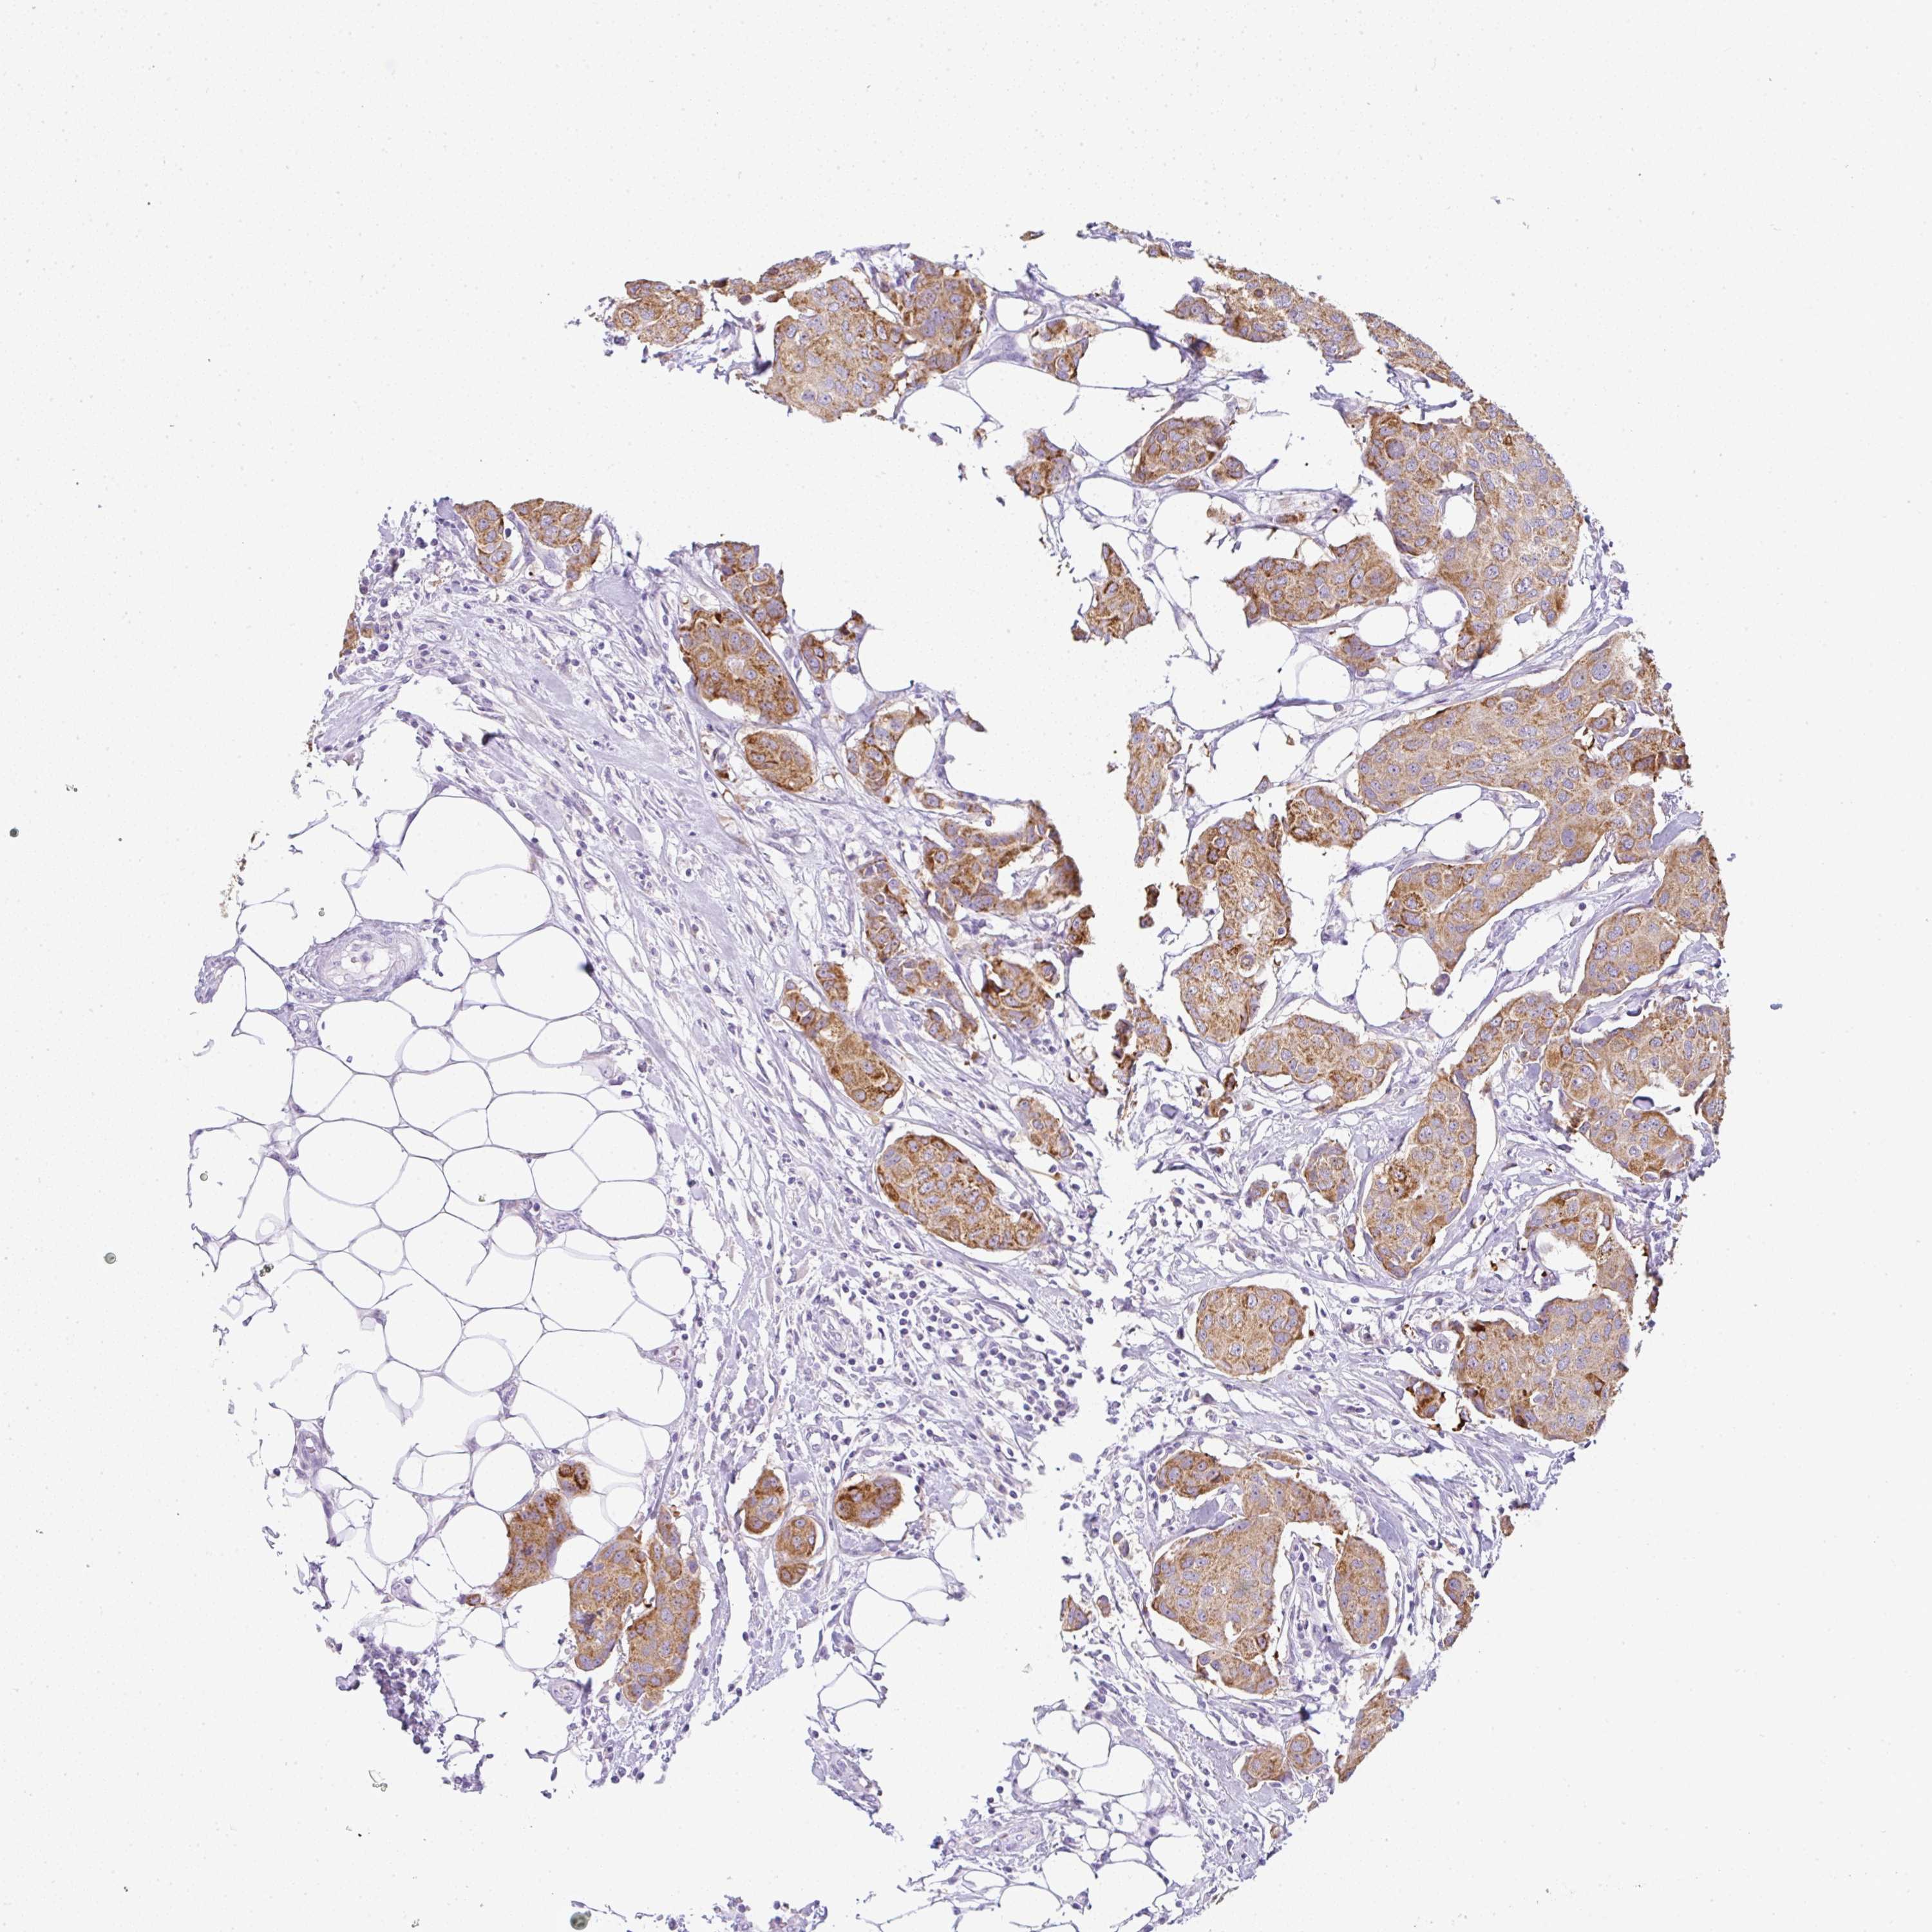

CANCER BREAST CANCER Show tissue menu

BRCA TCGA BRCA VALIDATION PROTEIN EXPRESSION

Breast cancer

Human cancer